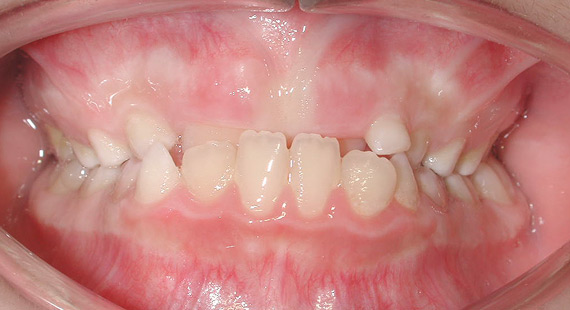

3 Les différents types de malocclusion:supraclusion

Un sujet très connu en orthodontie, qui est le mauvais alignement des dents :

Diverses raisons peuvent expliquer cette malformation, comme une bouche étroite, une différence de taille du maxillaire, un traumatisme suite à une chute, sucer son pouce, parler avec un cheveu sur la langue, etc. Le chirurgien-dentiste ou l’orthodontiste aura recours à un traitement orthodontique pour ajuster les mâchoires afin que celles-ci aient un positionnement correct. Plusieurs solutions sont possibles : la pose d’un appareil orthodontique fixe ou invisible, ou bien l'utilisation d’une gouttière. Le but de l'utilisation d'un appareil dentaire est d'effectuer une légère pression sur les dents afin que celles-ci soient poussées, jusqu'à ce qu'elles retrouvent un alignement optimal. La durée du traitement varie d’un patient à l’autre, selon l'ampleur du problème. La plupart du temps un appareil orthodontique demande à être porté durant deux ans.